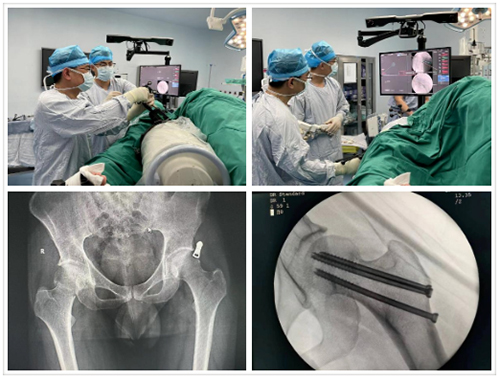

家住临沂市67岁的李大娘雪天摔伤左肩部,当地拍片显示左侧肱骨近端粉碎性骨折,遂来济南求诊,辗转多家医院后入住我院创伤中心东院区治疗。患者年龄较大,肱骨近端骨折粉碎且合并肱骨头脱位,即使手术勉强恢复其解剖关系,未来发生肱骨头缺血坏死、创伤性关节炎等并发症的几率极高。经过科室充分讨论分析,最终确定反式肩关节置换的手术方案。在李连欣教授和麻醉手术科以及护理团队的通力合作下,顺利完成反肩置换术,术中透视显示假体复位良好,患者左肩部恢复正常活动度。